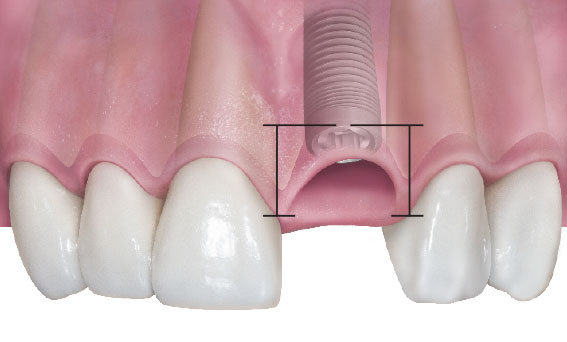

Вообще, по этому вопросу есть большая и очень подробная статья, посвящённая подбору и позиционированию имплантатов. Есть имплантологическое правило #2, гласящее, что

размер и положение имплантата должны соответствовать размеру и положению естественного зуба

Если быть более точным, то речь идёт о правильном положении и нужном размере ортопедической платформы (интерфейса), в то время как само тело имплантата служит для удержания платформы (достижения стабильности) и передачи жевательной нагрузки на челюстную кость:

Так вот, в контексте синуслифтинга, первичная стабильность имплантатов длиной 10 и 13 мм будет одинаковая, поскольку у них будет одинаковое пятно контакта с поверхностью кости

Это значит, что какой-то существенной разницы в использовании имплантатов разной длины (но одинакового диаметра) при установке одновременно с синуслифтингом нет. Однако, для имплантата большей длины нужно делать большое субантральное пространство — а это означает увеличение рисков, больший расход материалов, больший срок ожидания и т. д.